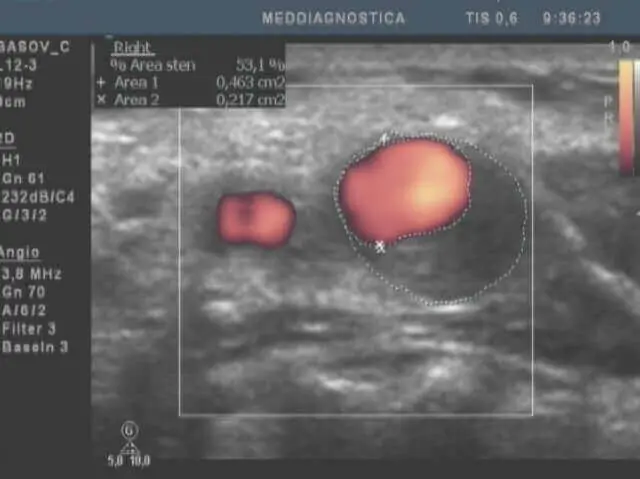

УЗД судин голови та шиї. Атеросклеротична бляшка у гирлі внутрішньої сонної артерії, стеноз 53% щодо поперечного перерізу судини (за площею). Червоним виділена прохідна частина судини, бляшка займає крайове становище у вигляді півмісяця.